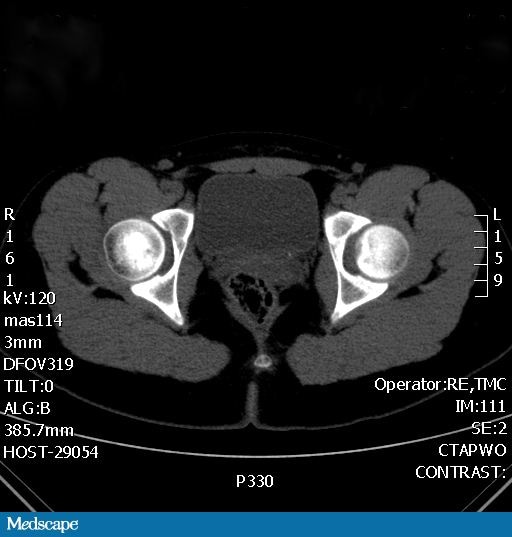

From www.medscape.com

Renal Stones in Kids Non Radiopaque Stones The goals of imaging of urinary calculi are to determine the presence of stones witin the urinary tract, evaluate for complications, estimate the likelihood of stone passage,. Others may be asymptomatic or have atypical. Patients may present with the classic symptoms of renal colic and hematuria. Calculi (stones) affecting the kidneys; Noncontrast ct is the most accurate imaging modality for. Non Radiopaque Stones.